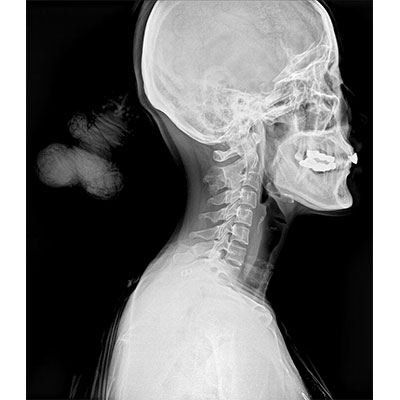

● 采用自主研發(fā)的技術,在保證優(yōu)質圖像的前提下,大大降低X射線劑量,用心呵護醫(yī)護工作者及患者的健康。

● 短曝光時間,便于老年人、兒童、殘疾人進行臨床拍攝。避免這類群體因不能有效控制身體運動等因素造成的運動偽影,提高攝片質量及效率。